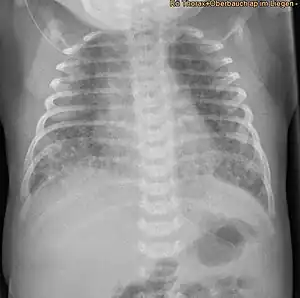

X-ray showing lung damage in response to meconium in a newborn.

Respiratory distress in an infant born through the darkly coloured MSAF as well as meconium obstructing the airways is usually sufficient enough to diagnose MAS. Additionally, newborns with MAS can have other types of respiratory distress such as tachypnea and hypercapnia. Sometimes it is hard to diagnose MAS as it can be confused with other diseases that also cause respiratory distress, such as pneumonia. Additionally, X-rays and lung ultrasounds can be quick, easy and cheap imaging techniques to diagnose lung diseases like MAS.[20]